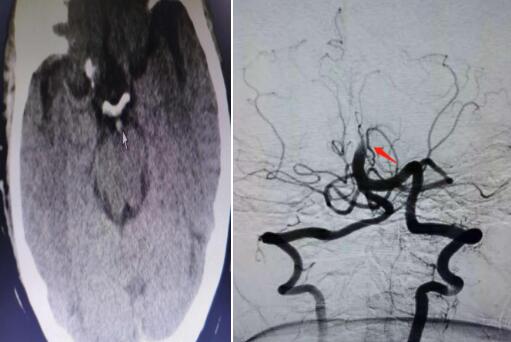

近日,我院開展市級醫(yī)院首例顱內(nèi)基底動脈溶栓術(shù)+取栓術(shù),成功搶救一名基底動脈尖綜合征患者。據(jù)市我院腦病科(神經(jīng)內(nèi)科)副主任楊波介紹,基底動脈尖綜合征是一種潛在的致命性神經(jīng)系統(tǒng)疾病。因基底動脈為腦干的主要供血系統(tǒng),是呼吸、心跳等中樞的生命線,所以,一旦發(fā)生腦干缺血閉塞,如不及時搶救,患者往往“非死即癱”...